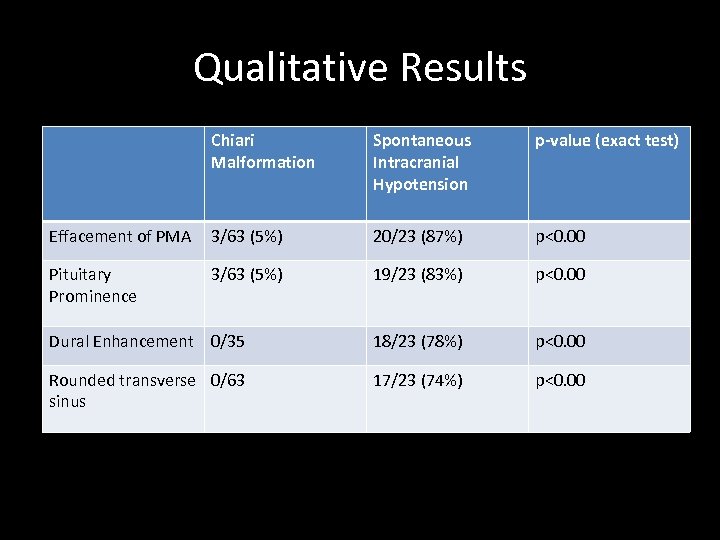

Qualitative Results Chiari Malformation Spontaneous Intracranial Hypotension p-value (exact test) Effacement of PMA 3/63 (5%) 20/23 (87%) p<0. 00 Pituitary Prominence 3/63 (5%) 19/23 (83%) p<0. 00 Dural Enhancement 0/35 18/23 (78%) p<0. 00 Rounded transverse 0/63 sinus 17/23 (74%) p<0. 00

Qualitative Results Chiari Malformation Spontaneous Intracranial Hypotension p-value (exact test) Effacement of PMA 3/63 (5%) 20/23 (87%) p<0. 00 Pituitary Prominence 3/63 (5%) 19/23 (83%) p<0. 00 Dural Enhancement 0/35 18/23 (78%) p<0. 00 Rounded transverse 0/63 sinus 17/23 (74%) p<0. 00